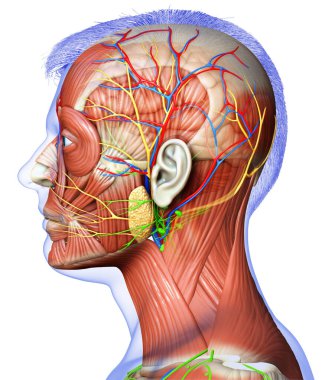

The arterial blood supply to the neck (carotids and vertebral arteries).

İnsanBaşıkanİlaçyüzboğazıBoyunresim çalışmasıprofilNormalbeyinarterkarotidKan damarıKan dolaşımıİnsan AnatomisiSerebral kan dolaşımıvaskülarizasyonsubclavian arteryortak Karotis arterbrachiocephalic Arteryel gövdeVertebral arterfacial arteryserebral artercervical arterytemporal arterydahili şah damarıharici şah damarıdeep cervical arteryBenzer İçerikler